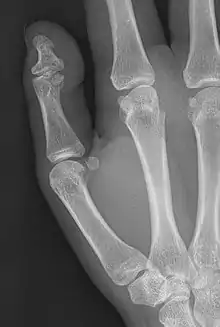

Brachyphalangy of the distal phalange of the thumb

This condition is caused by either fusion or early closure of the phalange's growth plate. One example is brachydactyly type D, which is caused by an early closure of the thumb's distal phalange, leading to a congenitally short thumb with a similarly short and wide thumb nail.